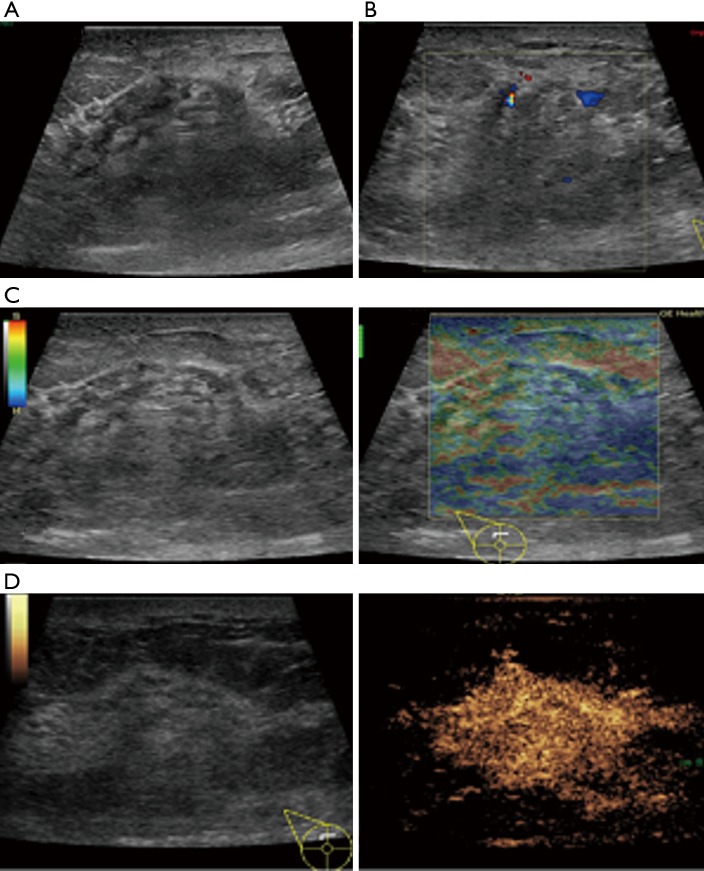

In this study, CEUS of LABC showed high enhancement, and its internal and peripheral blood vessels showed “solar sign” (Figure 1). Relevant studies showed (25) that angiogenic factors could stimulate the breast tissue to produce new blood vessels that extend into the tumor in malignant tumors. And then it would form a network of blood vessels that changed with the growth and necrosis of the tumor. Due to the anisotropy of malignant tumor growth, its internal vascular path was messy, twisted and variable. The characteristic of “solar sign” was often seen as an important indicator for the diagnosis of benign and malignant tumors (23,25). In this study, the tumors of invasive ductal carcinoma all presented as “fast in and slow out”. Analysis suggested that there might be abundant arterial regeneration in the tumor. They were rapidly enhanced. Related studies showed that malignant tumors were composed of abnormal blood vessels with increased tortuosity. It tended to increase flow resistance. At the same time, hypoxia and acidosis decreased red blood cell fluidity. They could also lead to venous insufficiency, poor reflux, and thrombosis, which leaded to form a slow withdrawal (27-29). Some study revealed that breast cancer presented as “fast in and fast out”. It might be because of the formation of arteriovenous fistula inside the tumor. However, Wan et al. [2012] (25) showed that the enhancement mode could also be “fast in and slow out” in benign tumors. It might be related to the blood supply characteristics of the breast tumor. So the mode of enhancement cannot be used as a distinguishing feature of benign and malignant breast tumors. In addition, in this study, 11 lesions (11/40, 27.5%) had no, equal or low enhancement areas, including 5 lesions (5/40, 12.5%) had no continuous enhancement areas. In 3 of the 5 lesions, the internal cystic area was found in conventional ultrasound, but the area of no enhancement in CEUS was significantly larger than that in conventional ultrasound. In 2 lesions, no cystic area was found in conventional ultrasound, but CEUS showed non-liquefaction necrosis area without enhancement (Figure 2). In addition, for non-mass breast cancer, it was difficult to be presented in conventional ultrasound. CEUS could show relatively clear boundaries. In particular, CEUS could clearly show the area of lesions and internal vascular conditions, assisting in diagnosis and guiding the area of puncture biopsy (Figures 3,4). Therefore, CEUS was more likely to detect muscle or skin infiltration than conventional ultrasound, providing a reference for accurate clinical T staging of LABC.

Figure 4.

The features of conventional ultrasound, SE and CEUS (non-mass type) of locally advanced invasive ductal carcinoma in 1 case. Female, 54 years old, right breast had mass for 2 months. (A) Conventional ultrasound showed the disturbance in right upper quadrant of breast. No specific boundary was observed; (B) it presented short striped blood flow signal in CDFI. Blood flow was rated grade II; (C) SE showed that the tumor boundary was not clear, and the visual score was 3 points; (D) CEUS showed that the lesions were highly enhanced with clear boundaries and blood vessels showed “solar sign”. CEUS, contrast-enhanced ultrasonography; CDFI, color Doppler flow imaging; SE, strain elastography.